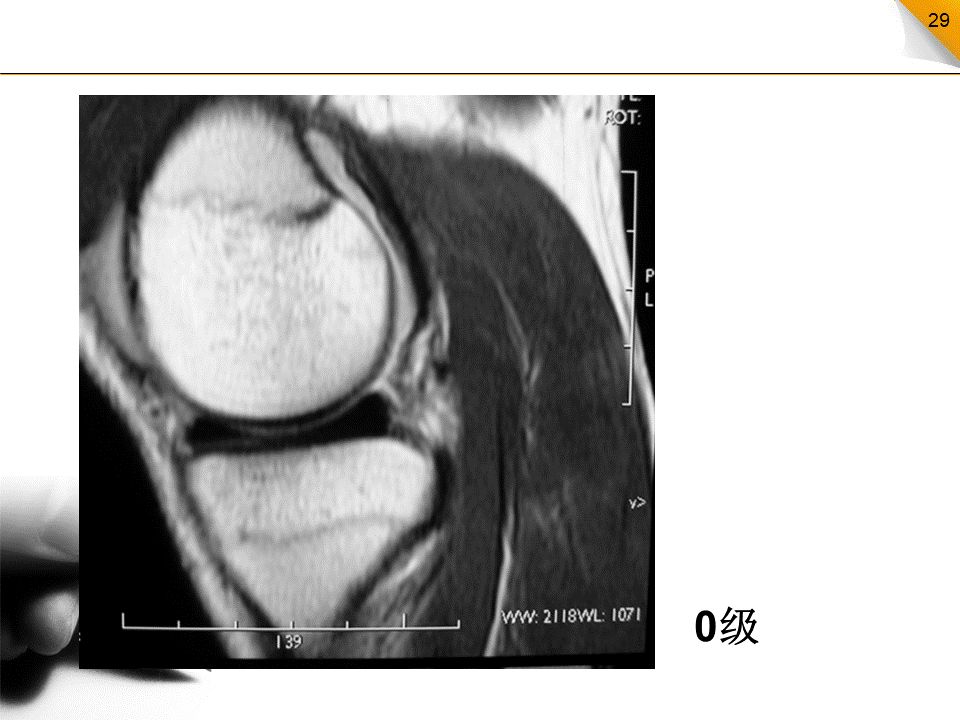

半月板损伤的MR分级

0级:正常半月板,均匀的低信号,形态规则I级:不与半月板关节面相接触的灶性信号增高影II级:半月板内线性信号增高,可延伸至半月板的关节囊缘,但未达到半月板的关节面缘,是I级信号改变的继续,范围更广III级:半月板内的高信号达到半月板的关节面,代表半月板的撕裂IV级:半月板破碎成多块并向关节腔内移位